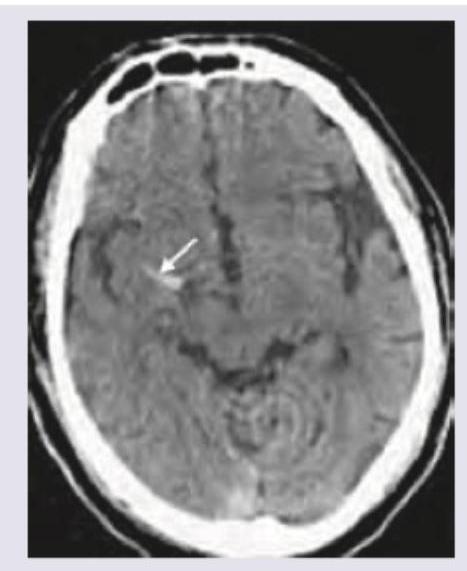

Question 9: A 55-year-old diabetic patient develops sudden onset hemiparesis and facial asymmetry. NCCT scan shows:

- A. Hyperdense MCA sign (Correct Answer)

- B. Cystic encephalomalacia

- C. Subarachnoid hemorrhage

- D. Lobar hemorrhage

Explanation: ***Hyperdense MCA sign*** - The image exhibits a **bright (hyperdense) area** within the Sylvian fissure, indicated by the white arrow, representing a **thrombus occluding the middle cerebral artery (MCA)**. This is a direct sign of acute **ischemic stroke**. - Clinical presentation of sudden onset hemiparesis and facial asymmetry in a diabetic patient strongly suggests an **ischemic stroke**, and the hyperdense MCA sign on NCCT confirms a proximal vessel occlusion. *Cystic encephalomalacia* - This refers to the **end stage of an infarct**, where brain tissue is replaced by **CSF-filled cysts** and gliosis, appearing as hypodense areas. - This finding would indicate an **old stroke**, not an acute event causing sudden neurological deficits. *Subarachnoid hemorrhage* - This condition involves **blood in the subarachnoid space**, appearing as hyperdensity within the **sulci and basal cisterns**. - While it features hyperdensity, the location in the image (within the Sylvian fissure, consistent with MCA) and the patient's symptoms are not typical for isolated subarachnoid hemorrhage. *Lobar hemorrhage* - A lobar hemorrhage is an **intraparenchymal bleed** within a lobe of the brain, appearing as a **focal, well-defined hyperdense lesion within the brain parenchyma**. - The hyperdensity in the image is linear and located within a vascular structure, consistent with an occluded vessel rather than a parenchymal bleed.